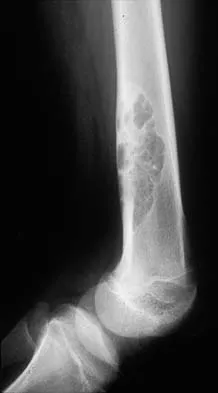

A previously asymptomatic 14-year-old girl sustained a twisting injury to her ankle. Radiographs are shown in Figures 2a and 2b. Management should consist of

Explanation

The radiographs show a well-defined, irregular, eccentric lesion in the distal tibia metaphysis with a thin sclerotic margin. The radiographs are diagnostic of nonossifying fibroma, a common entity in this age group and in this location. No further work-up is indicated. The patient was asymptomatic prior to the injury and the lesion is small and thus not worrisome for an impending pathologic fracture; therefore, no treatment is indicated beyond observation. The natural history of these lesions is to gradually ossify as the patient reaches skeletal maturity. Menendez LR (ed): Orthopaedic Knowledge Update: Musculoskeletal Tumors. Rosemont, IL, American Academy of Orthopaedic Surgeons, 2002, pp 69-75.